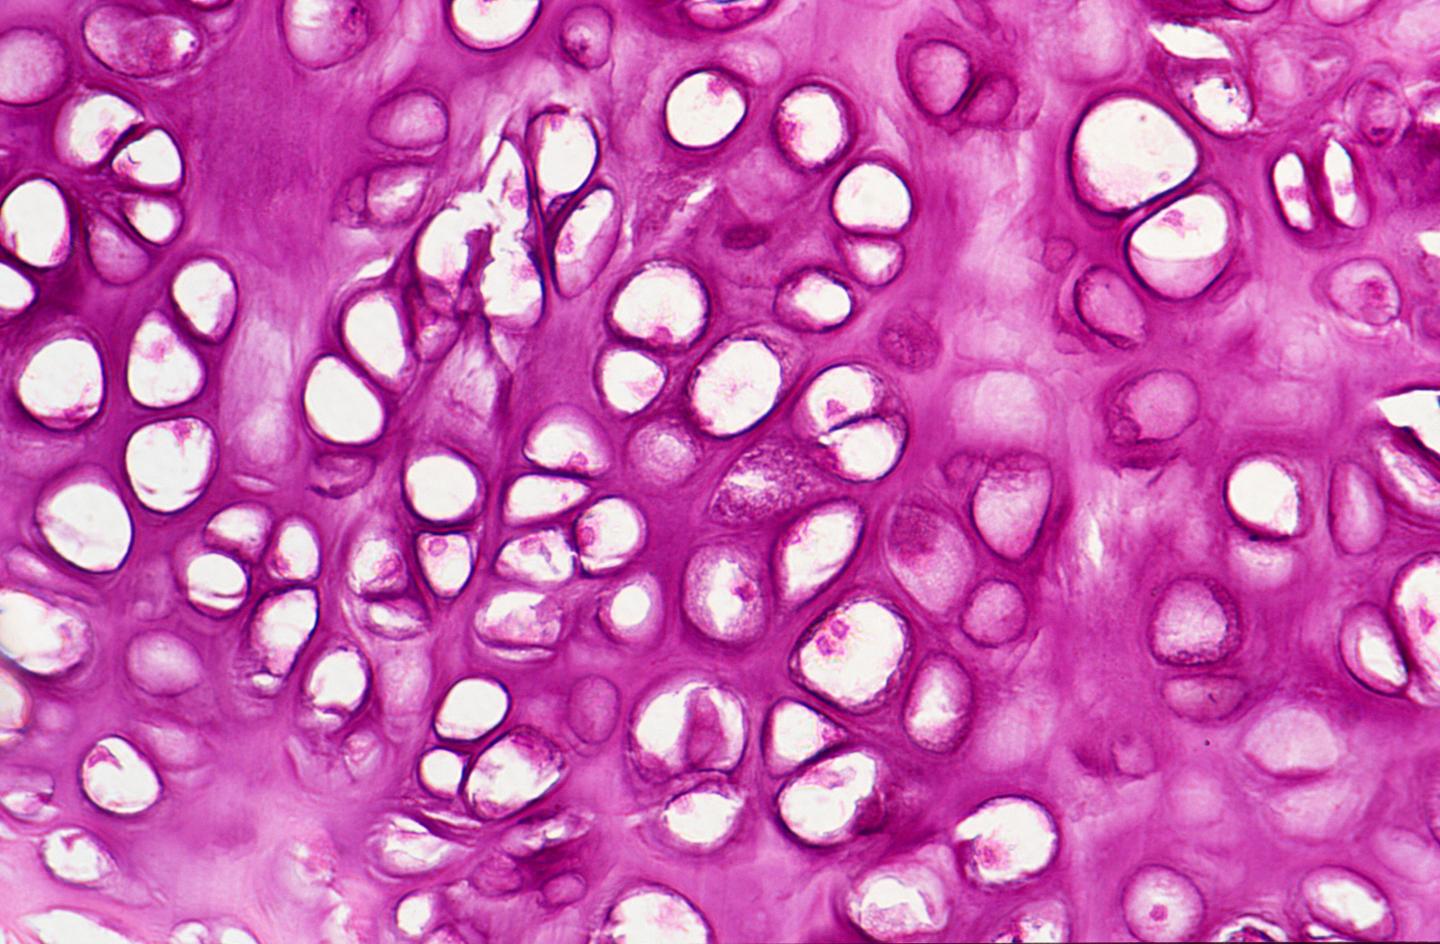

image: Chondrocytes.

Vosoritide is a synthetic version of a protein present in humans called C-type natriuretic peptide. It is designed to bind to a specific receptor on the surface of chondrocytes, a type of cartilage cell found in the growth plates of bones. Once joined, the vosoritide-receptor connection sends a signal inside the fibroblast to stanch the flow of negative growth factors that were triggered by the mutation in the FGFR3 gene.